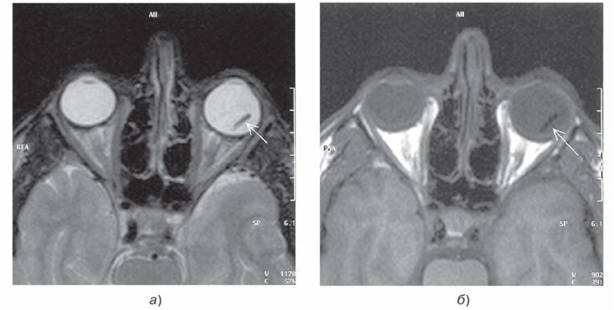

Рис. 92. МР-томограммы глазниц в аксиальной плоскости. Т2-взвешенные изображения (а) и Т1-ВИ (б). Инородное тело глазного яблока (стрелка).